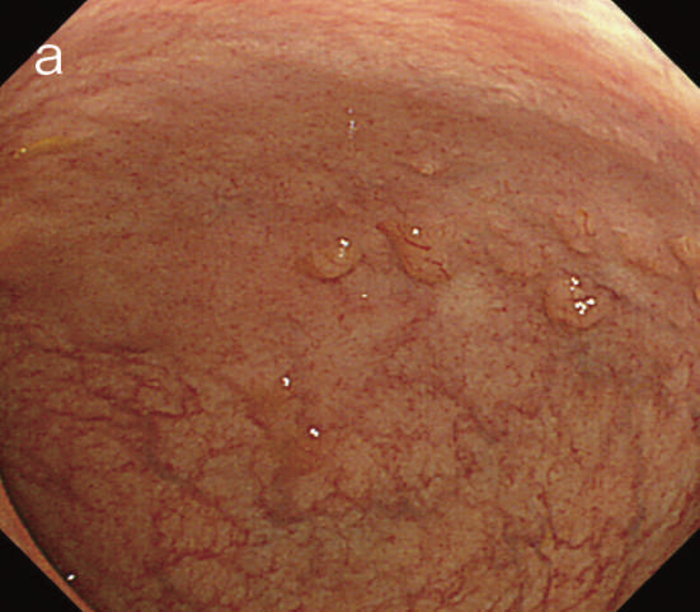

図5 UC関連粘膜下層浸潤癌の内視鏡所見

- 白色光像:直腸(直腸S状部)の発赤調変化。背景粘膜は寛解期にあった。

- 色素内視鏡像:病変辺縁が明瞭となるが,病変肛門側で不明瞭であった。

- NBI拡大像:口径不同,不均一な微小血管と不整な表面構造所見を認めた。

- pit pattern像:小型の類円形,管状pitを認めた。